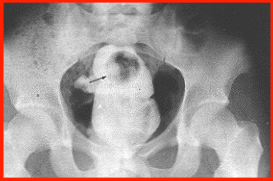

of the rectum revealed a stony hard mass. Abdominal plain films showed

a vertically oriented, low-lying radiopaque object in the rectum.

A spherical radiolucency was noted

in the upper pole of the mass. A blood alcohol level was negative.

Examination of the specimen revealed a perfect concrete cast of

the rectum, measuring 12 X 7 X 5 cm and weighing 275 g (Fig. 2). A thin layer of feces coated the

surface and crevices. Grooves in the mass were consistent with rectal

mucosal folds. A layer of concrete was chipped off the upper part

of the specimen and revealed a white plastic ping-pong ball. This

corresponded to the radiolucency observed in the abdominal x-ray.